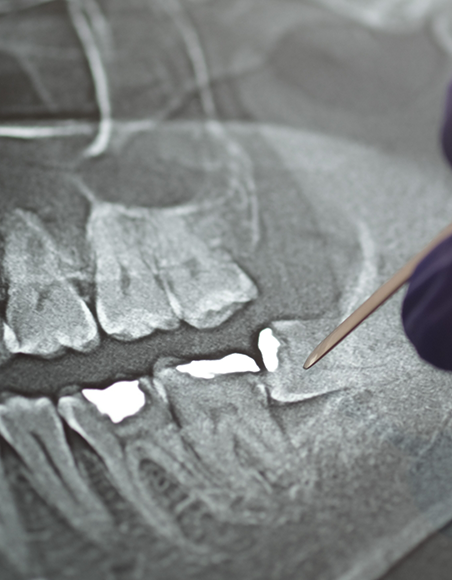

Safe mercury removal refers to a specialized process for removing amalgam fillings in a way that reduces mercury exposure for both patients and dental staff. Traditional amalgam fillings contain mercury, a heavy metal that can release harmful vapor during removal if not handled properly. Our method includes: